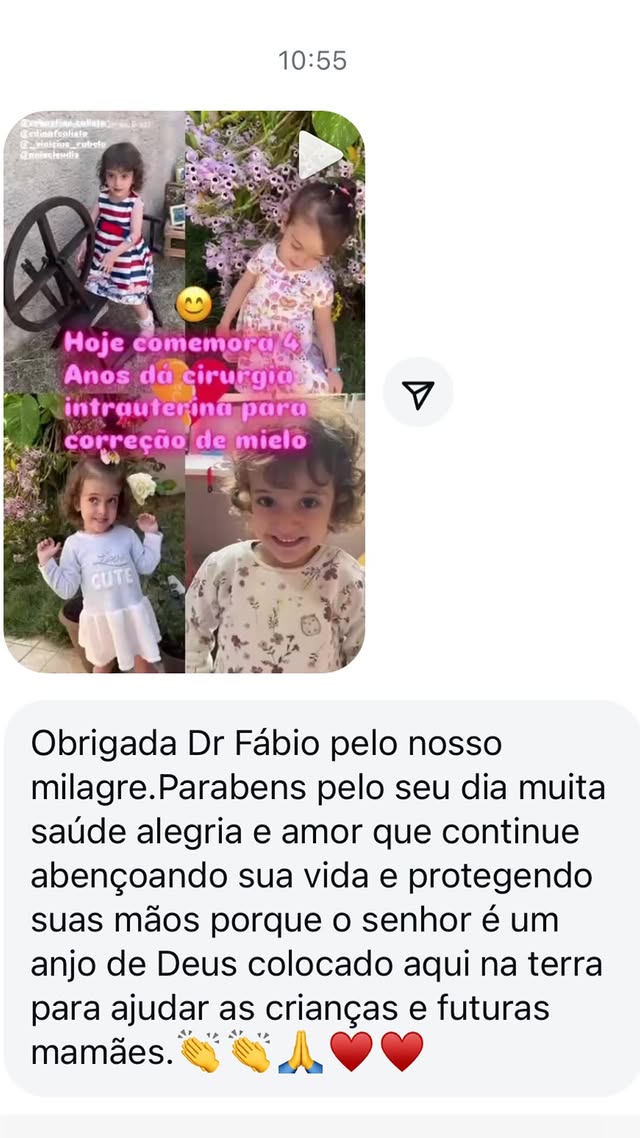

Esperança viva: descubra o futuro

que a Valentina conquistou

"Valentina é a prova de que a força nasce junto com a vida. Hoje inspira todos ao seu redor com sua coragem. Sua trajetória mostra que, com apoio, fé e amor, é possível transformar desafios em conquistas. Essa é a história de uma menina que não se limitou ao diagnóstico, mas abraçou o futuro com esperança viva."